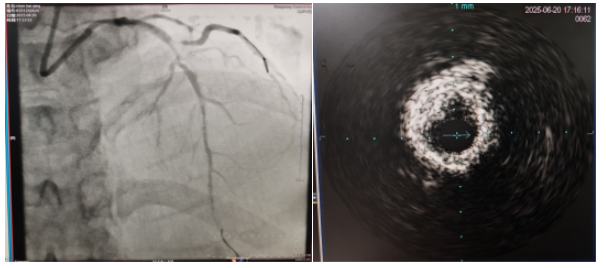

術中,趙慶禧主任醫(yī)師、雷剛副主任醫(yī)師運用IVUS血管內超聲技術評估,發(fā)現(xiàn)患者前降支、對角支0.1.1型真性分叉病變,前降支近中段嚴重鈣化、成角并99%狹窄,對角支近段嚴重鈣化并99%狹窄,傳統(tǒng)冠狀動脈旋磨術容易引起冠狀動脈穿孔,決定采用沖擊波球囊技術即血管內沖擊波鈣化碎裂術對患者嚴重鈣化的血管進行介入治療。通過球囊低壓擴張,向血管病變處發(fā)射非聚焦、低能量、脈沖式的沖擊波,對前降支及對角支進行了連續(xù)5個周期沖擊波脈沖治療,安全地碎裂淺、深層鈣化,原本看似堅不可摧的環(huán)形鈣化區(qū)逐漸顯現(xiàn)出了裂痕,多處關鍵位置發(fā)生了斷裂,充分預處理后于前降支近中段串聯(lián)植入支架3枚,對角支植入藥物球囊,術后造影見血管病變處狹窄完全消失,支架膨脹完全,貼壁良好,各項生命體征平穩(wěn),手術非常成功,患者返回心血管內科病房繼續(xù)治療,并于4天后順利出院。